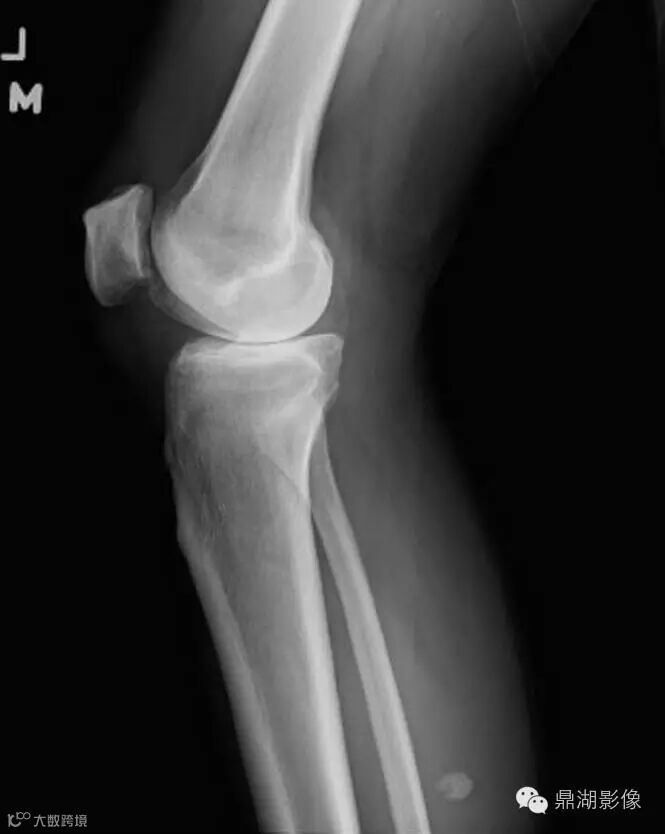

An 81-year-old man presents to the emergency department with pain and swelling of the left knee and calf. Left knee radiographs were obtained

1.1 What pertinent findings are demonstrated on the images below?

Ok ,let's go on,the correct answer is ABD

解析:A.Osteoarthrosis is correct. There is joint-space narrowing, osteophyte formation, and subchondral sclerosis.

B. Calcification is seen within the posteromedial aspect of the upper calf soft tissues.

C.An avulsion fracture is not present to suggest an underlying ligamentous injury.

Lateral view of the left knee demonstrates joint-space narrowing (yellow arrow) and chondrocalcinosis (blue arrow). There is a calcified body (white arrow) within the inferior recess of a dissecting Baker cyst.

Lateral view of the left knee from two years prior shows the body positioned posterior to the femoral condyles (white arrow).